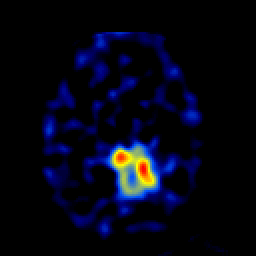

SPECT TL Study #4 -- Slice #37